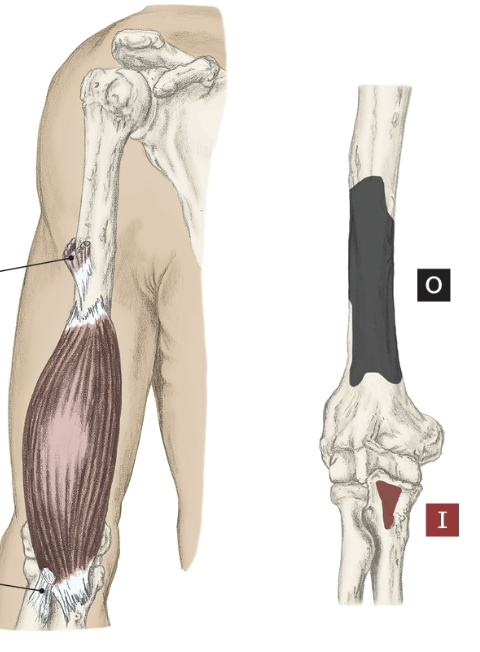

Action of the Brachialis

Elbow flexion

Origin of the Brachialis

Distal half of the anterior surface of the humerus

Insertion of the Brachialis

Coronoid process of the ulna and tuberosity.

Nerve that the Brachialis innervates

Musculocutaneous